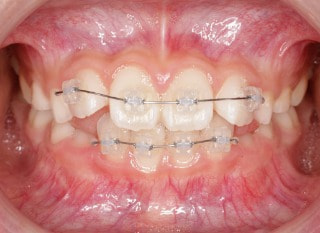

前歯装置装着時

治療中

小児期の第二段階

終了時